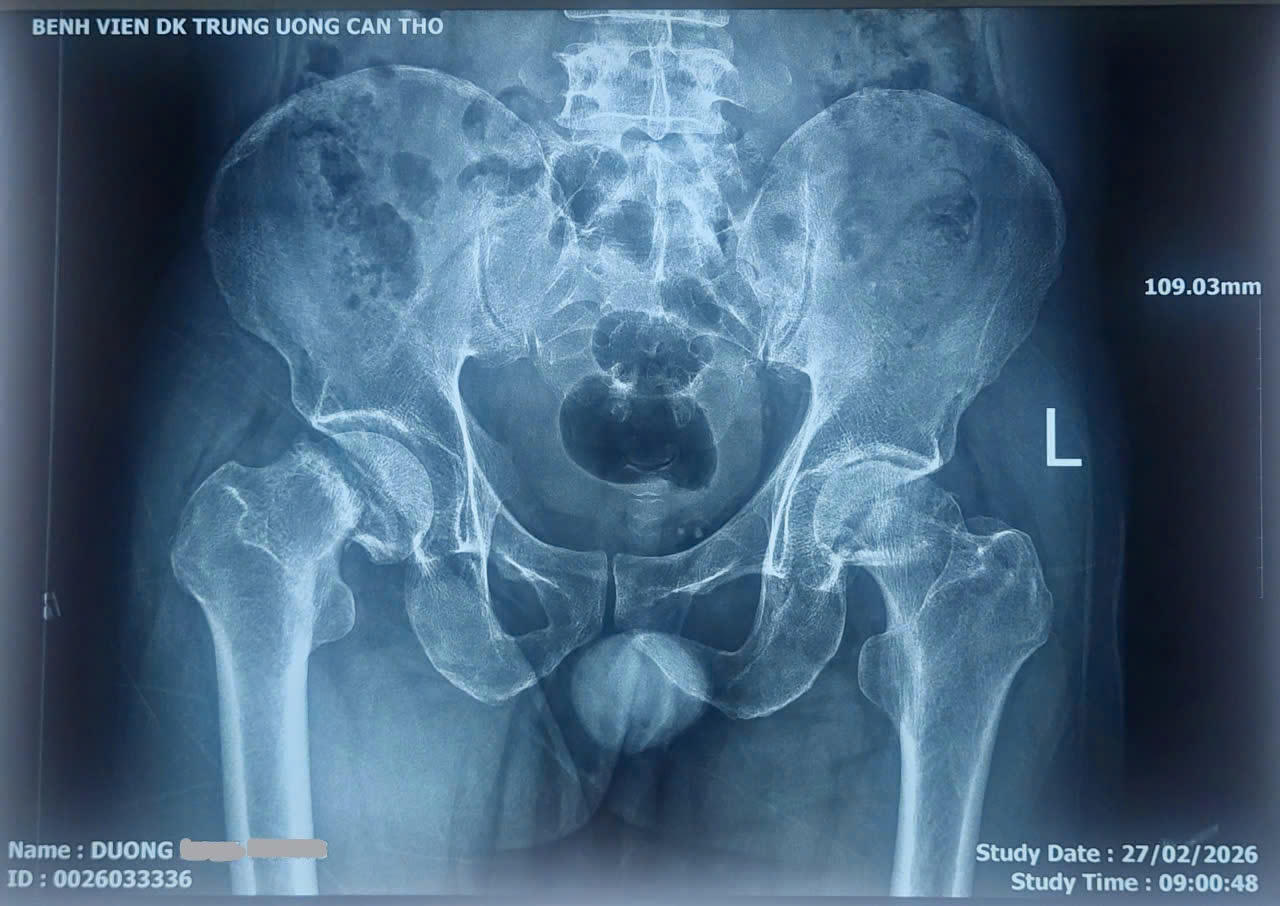

Bệnh nhân là ông D.H.P. (SN 1977, ngụ TP Cần Thơ) nhập viện trong tình trạng đau khớp háng hai bên kéo dài nhiều năm, việc đi lại khó khăn và phải thường xuyên dùng thuốc giảm đau. Các bác sĩ xác định bệnh nhân bị hoại tử chỏm xương đùi hai bên. Trước tình trạng này, bệnh nhân được chỉ định phẫu thuật thay khớp háng.

Các bác sĩ lựa chọn kỹ thuật thay khớp háng bằng đường mổ trực tiếp phía trước, một phương pháp ít xâm lấn hiện đại. Ca mổ kéo dài khoảng 4 giờ và tiến hành thay khớp háng hai bên trong cùng một lần phẫu thuật.